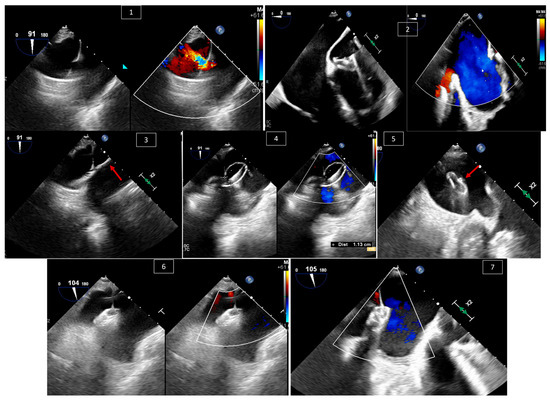

Echocardiography for Congenital Heart Disease: Fundamental。Congenital heart disease in echocardiography (an approach。Echo Tutorial: Echo Assessment of Adults with Congenital。 現在、1名がこの商品を検討中です

Utilizing Fetal Heart Ultrasound for Congenital Heart

Utilizing Fetal Heart Ultrasound for Congenital Heart

EchocardiographyinPediatricandAdultCongenitalHeartDisease-avolumeintheexcitingnewPracticalEchocardiographySerieseditedbyDr.Cather…